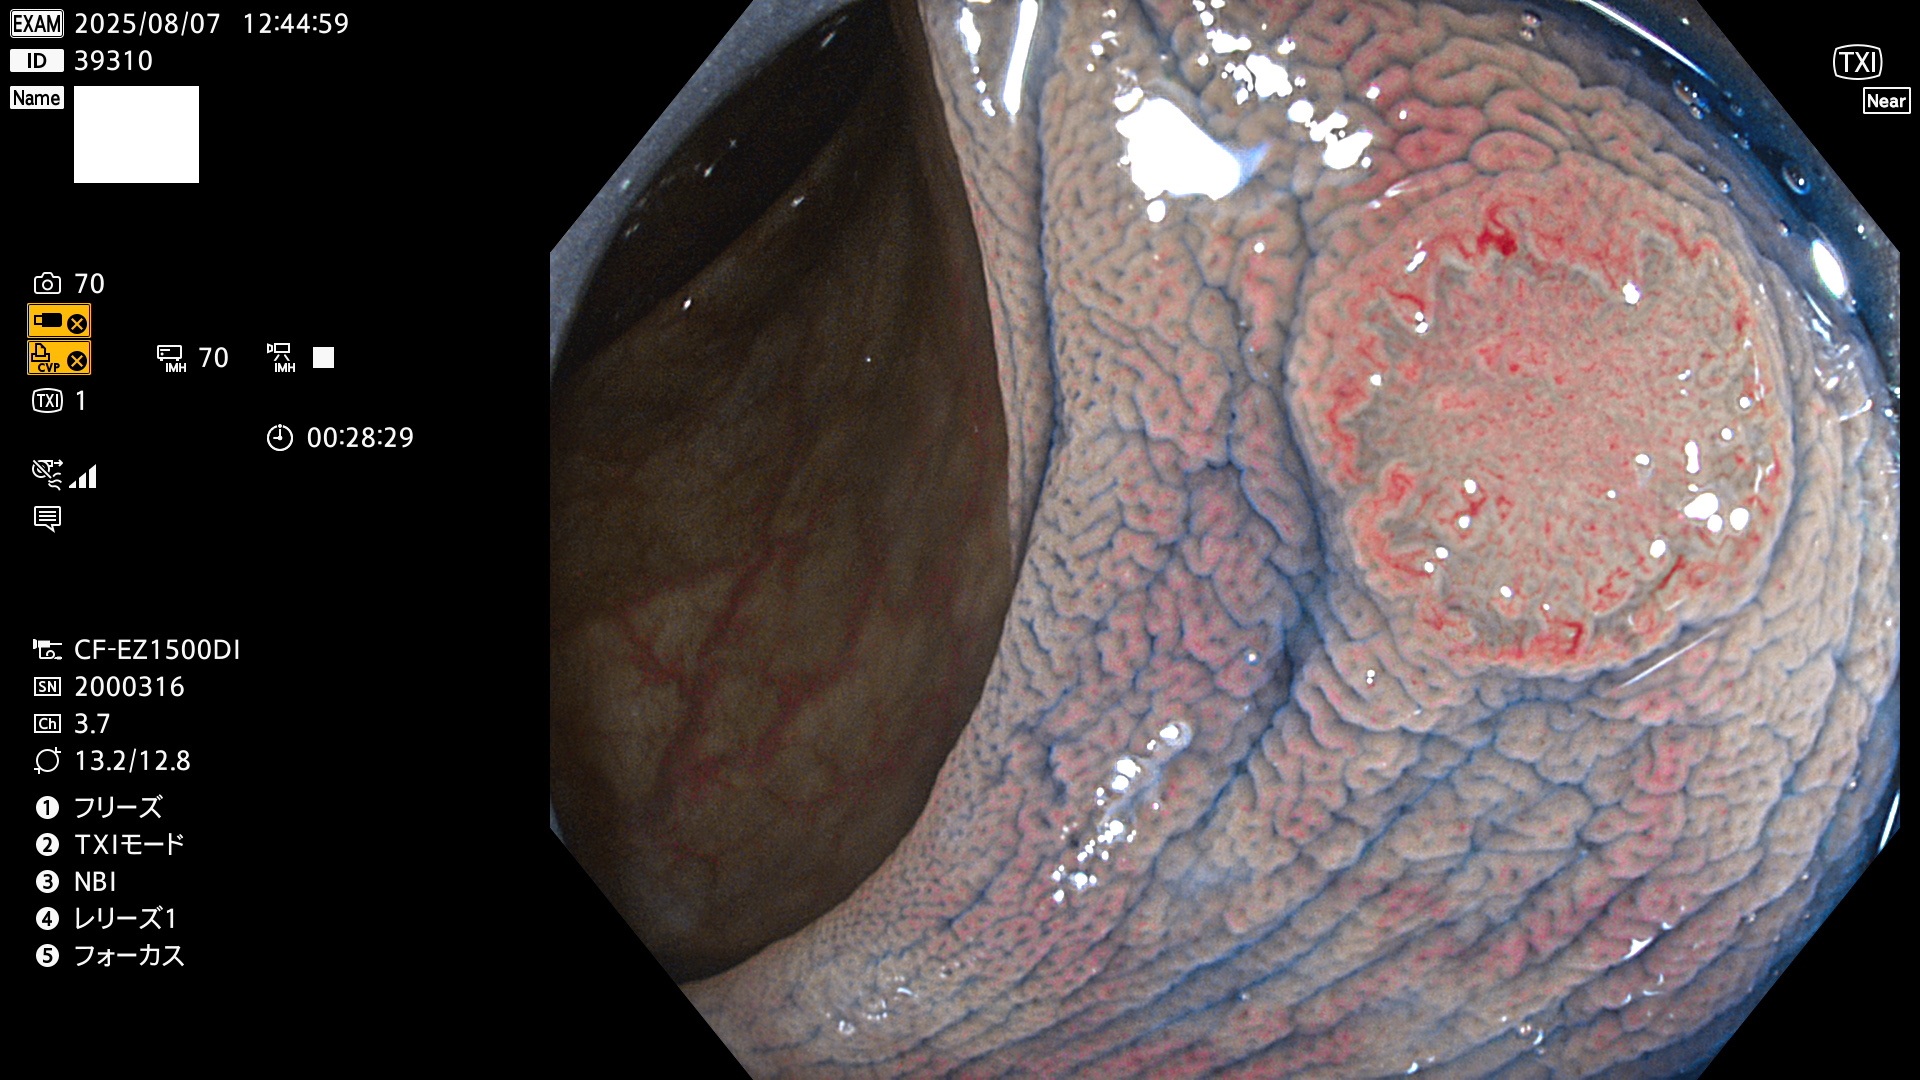

完全に平坦な物をUb、陥凹している物をUcと呼びます。Ubは認識が困難で、Ucはびらん(炎症)と紛らわしいために見落とされやすく、「内視鏡後・大腸癌」の原因になります。

毎週の検査(木・金・土・日)に発見されたUbとUc型・腺腫を、その週の日曜の夜にUPし1週間、提示します。

2025年8月7日〜8月10日の4日間(35件)6個 (Uc_ADR=6個/35人=17%)